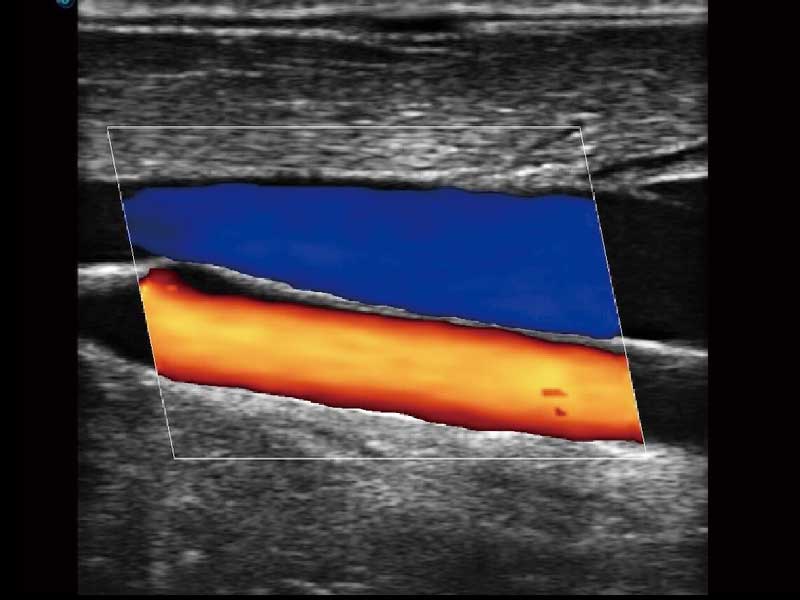

E2便携式彩色多普勒超声诊断系统采用专业的超声技术平台、高度集成化的硬件模块和结构设计、简便的操作流程、多探头接口设计,兼顾了优质图像、轻便机身以及台便两用的临床使用需求。

μ-Scan微米成像、空间复合成像、高分辨率血流成像。

临床图